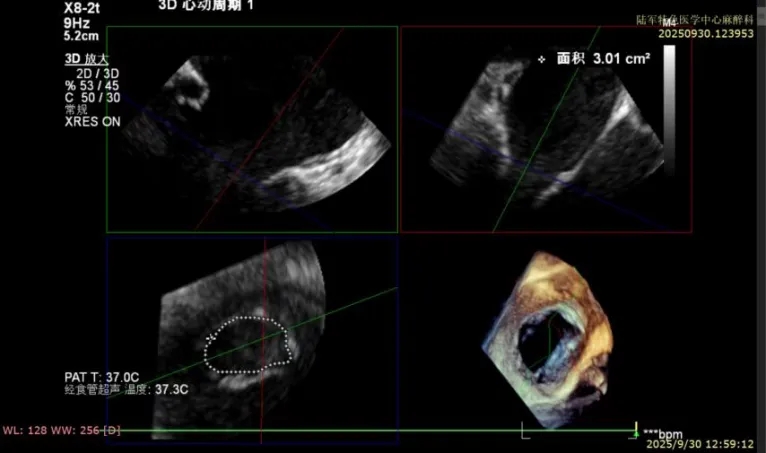

然而,心脏超声检查又带来致命一击,其结果显示,患者瓣口面积仅3.01cm²,房间隔高度仅3.8cm,且瓣叶组织脆弱、活动度差,这些心脏解剖结构指标均远低于常规手术安全范围。这意味着操作空间极其狭小,导管在心脏内的移动幅度受到严格限制,对器械的操控精度要求极高,任何微小偏差都可能导致严重并发症。这对手术团队的技术稳定性、心理素质和团队配合度提出了近乎极致的挑战。